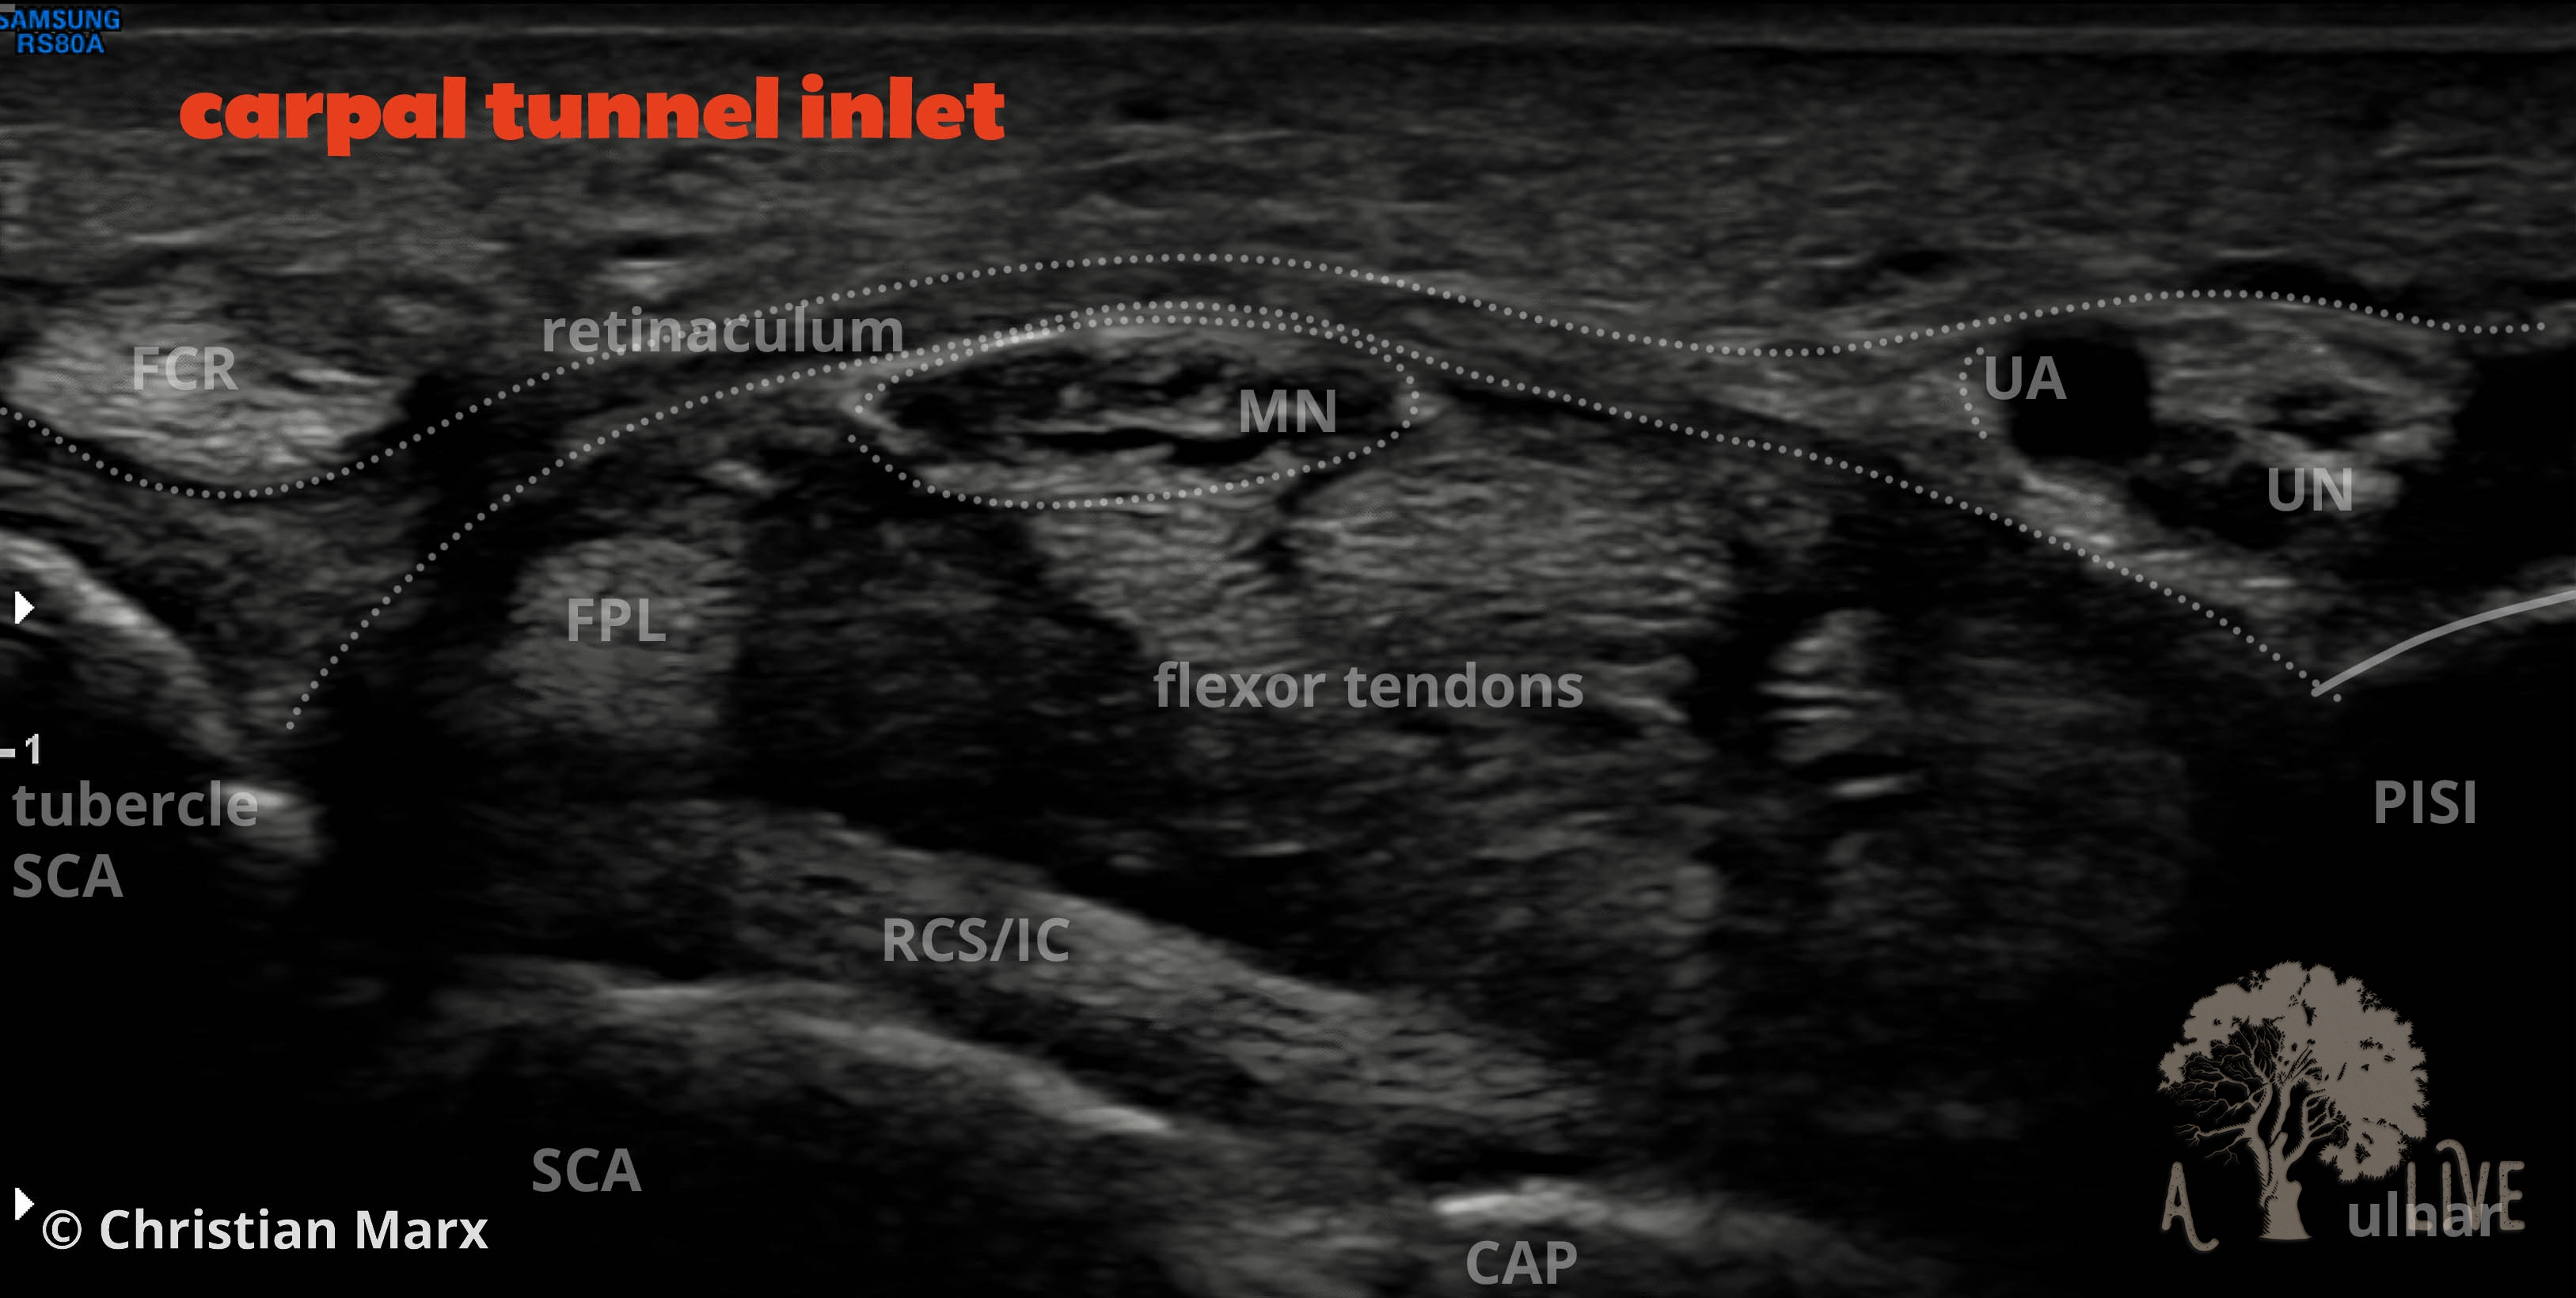

nerves of the wrist